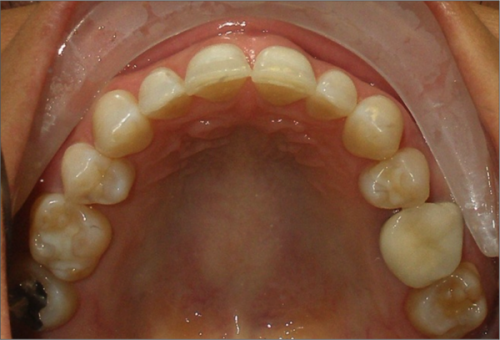

45 year old female:

Diagnosis:

- Missing upper left second bicuspid

- Lower arch crowding

- Edge to edge bite

Treatment:

- Extraction of upper & lower right second bicuspids

- Full fixed appliances

- 21 months